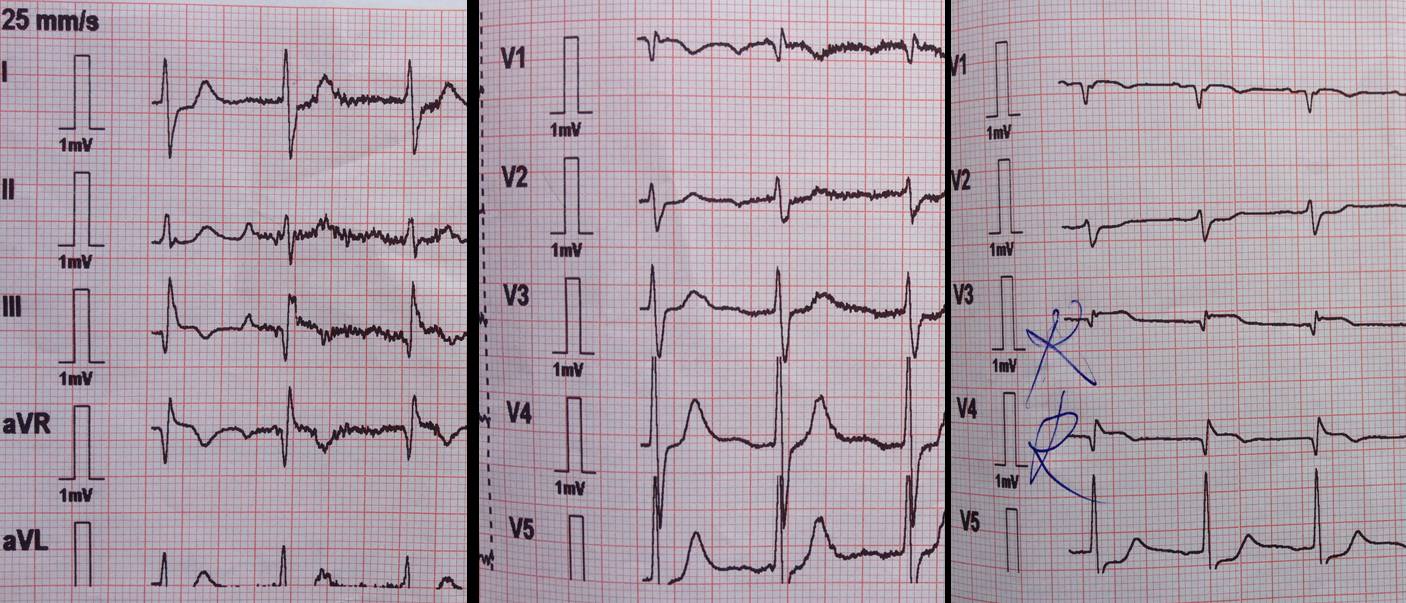

ECG la prezentare arată ritm sinusal cu AV= 90bpm, supradenivelare de segment ST DIII, aVR, derivatiile drepte maxim 1mm cu unde T negative la acest nivel, subdenivelare de segment ST DI, aVL (figura 1). Pe baza datelor clinice si paraclinice se stabileste diagnosticul de sindrom coronarian acut cu supradenivelare de segment ST la 3 ore de la debut cu stop cardiorespirator resuscitat. Se decide efectuarea coronarografiei de urgenta.